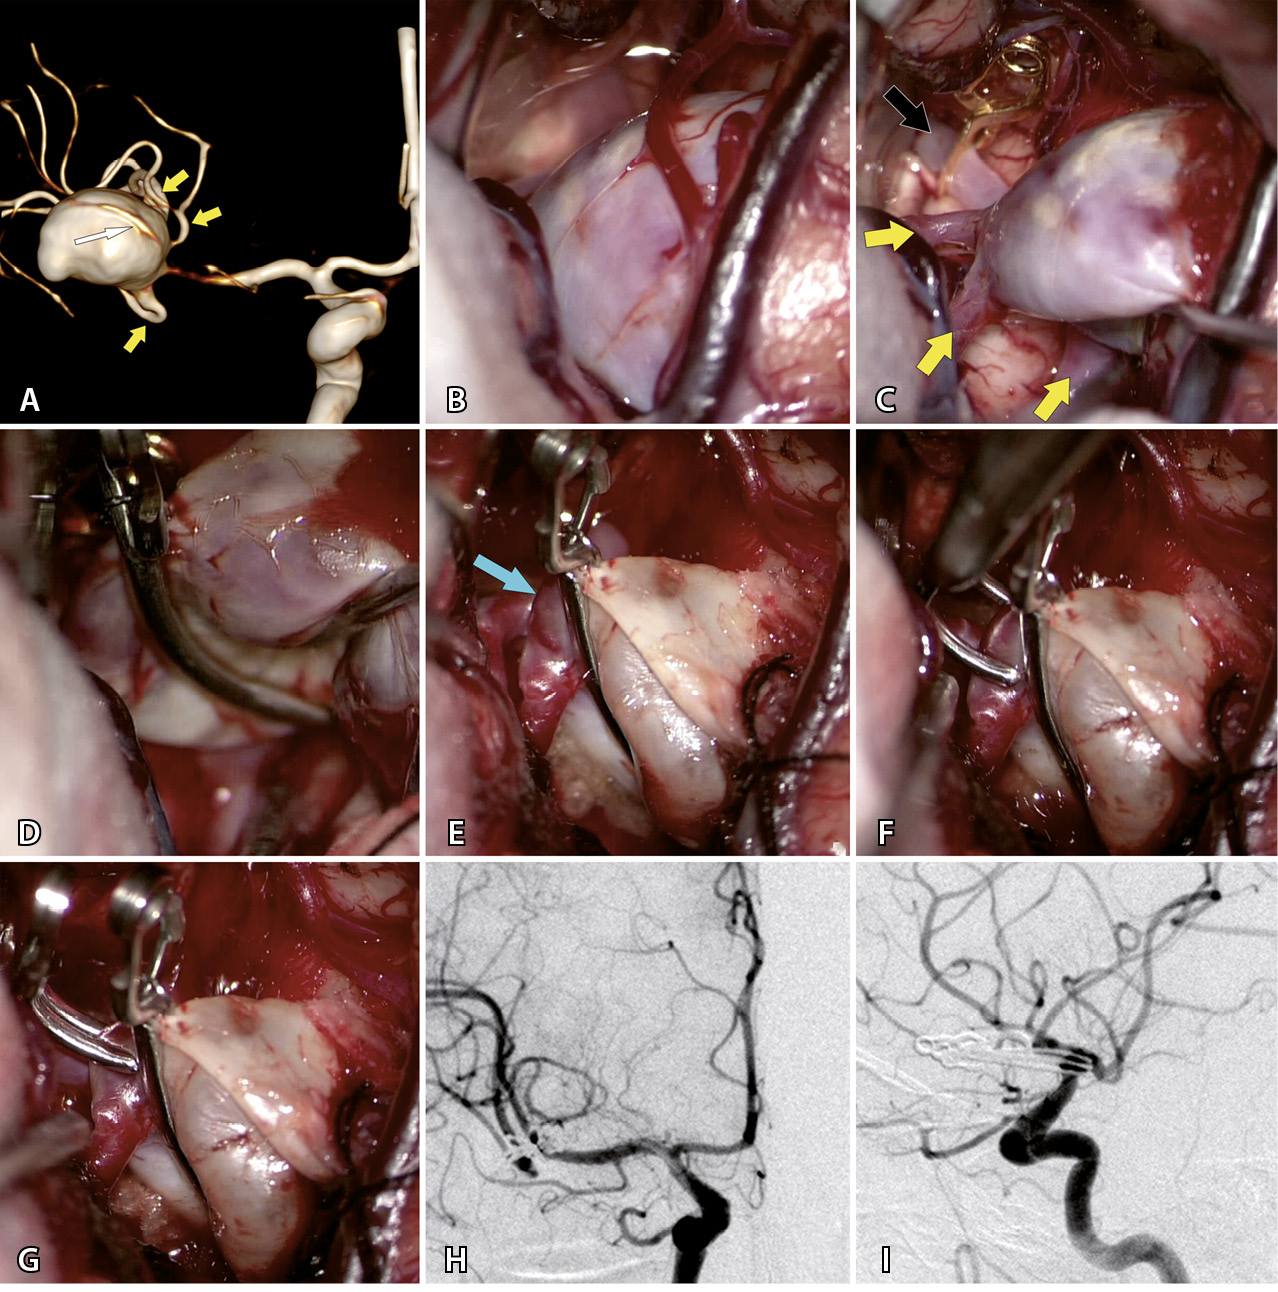

Операции с созданием байпаса сделаны в 19 случаях. Байпас перед треппингом аневризмы выполнен у 10 пациентов (в 8 случаях после треппинга проведена тромбэктомия). В 3 случаях при фузиформных гигантских аневризмах проведено проксимальное клипирование с целью создания возможности ретроградного кровоснабжения ветвей, выходящих из аневризмы. У 4 пациентов была реваскуляризация одной из М2-ветвей, где гигантская аневризма клипирована вместе с устьем данной ветви. В 2 случаях потребность в анастомозе возникла как экстренная мера вследствие тромбоза одной из ветвей СМА после КШ. Наиболее частым (n = 15) байпасом был микроанастомоз между М2–М4 ветвью СМА и поверхностной височной артерией (ПВА). Пример представлен на рис. 2. Микроанастомозы с двумя ветвями ПВА выполнены в 6 случаях. Высокопоточный байпас между наружной сонной артерией и М2-сегментом СМА с использованием графта лучевой артерии выполнен в 3 случаях при гигантской аневризме М1-сегмента. В 1 наблюдении произведена местная реимплантация одной М2-ветви в другую.

Рис. 2. Треппинг с тромбэктомией гигантской фузиформной частично тромбированной аневризмы М2-сегмента средней мозговой артерии (СМА) после создания экстра-интракраниального микроанастомоза у пациента Т., 69 л. А – компьютерная томография до операции: определяется гигантская частично тромбированная аневризма правой СМА. Б – компьютерная томографическая ангиография (3D) до операции: видна функционирующая часть фузиформной частично тромбированной аневризмы М2-сегмента правой СМА. В – интраоперационное фото: вид аневризмы после препаровки сильвиевой щели. Г – анастомоз между поверхностной височной артерией и М2-сегментом СМА. Д – треппинг аневризмы (стрелкой указан анастомоз). Е – вид аневризмы после тромбэктомии из ее полости. Ж – флюоресцентная видеоангиография: видно хорошее контрастирование шунта через анастомоз и заполнение М2-ветвей (стрелками указано направление кровотока). З – компьютерная томографическая ангиография (3D) после операции: аневризма не контрастируется и хорошо заполняется экстра-интракраниальный анастомоз. И – компьютерная томография головы после операции